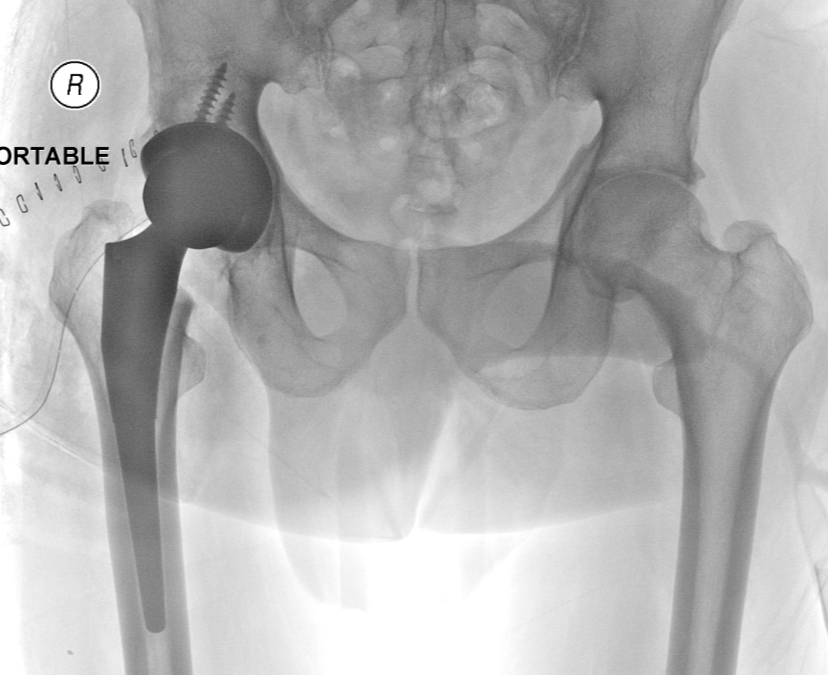

What is a total hip replacement?

It is a procedure in which the surgeon removes a painful or a worn off  hip joint and inserts an artificial joint.

The surgeon makes a cut along the side of your hip, moves the muscles connected to the top of the femur (thighbone), and exposes the hip joint. The surgeon pulls the ball portion of the joint (the end of the femur) away from the socket part of the joint (the hipbone). The ball of the femur is cut with a saw and an artificial replacement part is attached.

The surgeon prepares the surface of the hipbone and, if it is worn, attaches a metal or plastic socket part to the hipbone. The surgeon inserts the new ball part of the femur into the socket part of the hip. Two drains may be inserted to help drain any fluid or blood from the new joint. The surgeon then reattaches the muscles to the top of the femur and closes the cut in the side of your hip.